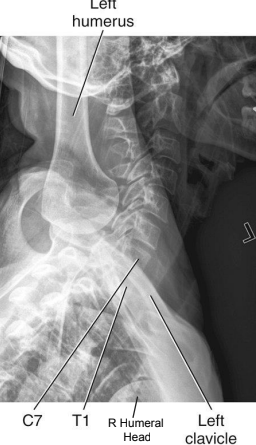

Swimmers: Eval Criteria

CR to T1

Vertebral bodies and intervertebral disk spaces of C5 to T3 are shown

Humeral head and arm farthest from the IR are magnified and appear inferior to T4 or T5

Minimal vertebral rotation indicated by superimposition of cervical zygapophyseal joints and articular pillars, and posterior ribs

Humeral heads should be separated vertically

Swimmers: Is this Image Good?

No

CR is too low

Move up to T1

Foggy, noisy, low contrast (underexposure)

Increase kVp